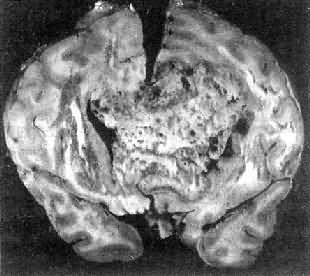

肉眼观,肿瘤呈球形,分叶状或不规则形,质实或硬,边界清楚,周围脑组织受压成凹陷切迹(图16-27)。少数肿瘤呈斑块状覆盖较广泛区域,甚至整个脑半球,称为斑块型脑膜瘤。肿瘤质地硬,切面灰白色,呈颗粒状、条索旋涡状,有的质地似砂砾样,乃由于有多量砂粒体存在。

图16-27 脑膜瘤

于大脑两半球间有一近似球形肿瘤,边界清楚,周围脑组织受压萎缩